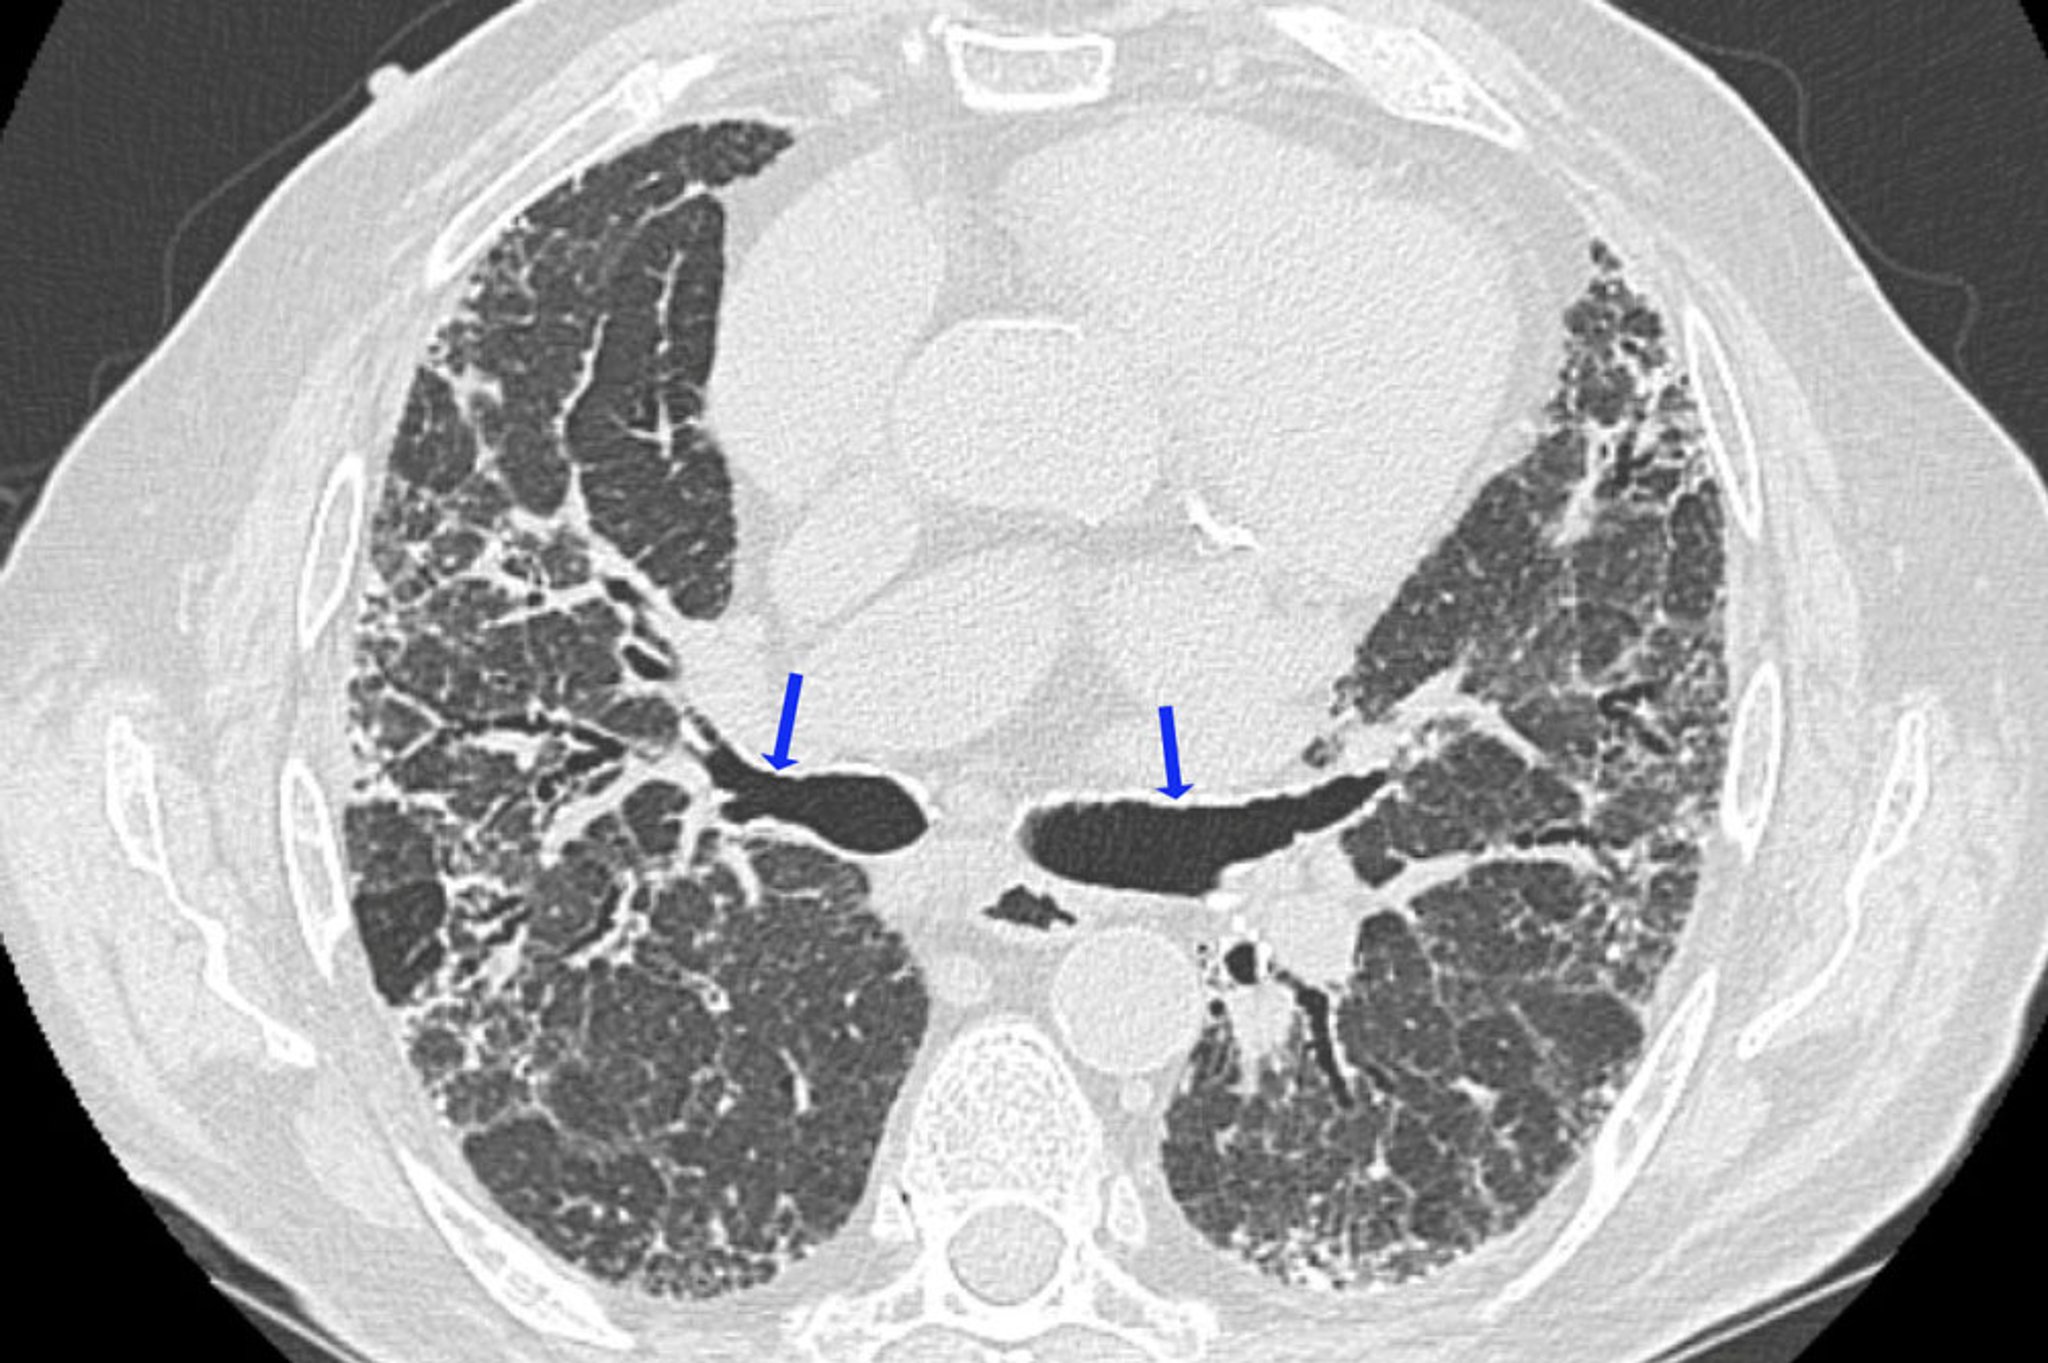

La TDM à haute résolution est la modalité d'imagerie préférée pour évaluer les changements parenchymateux dans la pneumopathie d'hypersensibilité, et est plus susceptible de montrer des anomalies que la TDM standard ou les radiographies (2).

Dans la pneumopathie d'hypersensibilité aiguë et subaiguë, les signes à la TDM à haute résolution les plus typiques sont des micronodules centrolobulaires, mesurant généralement moins de 3 mm de diamètre, habituellement situés près des voies respiratoires centrales de ces lobules. Parfois, l'opacité en verre dépoli (atténuation) est prédominante ou est parfois le seul élément retrouvé. Elle est habituellement diffuse, mais, parfois, elle épargne la périphérie du lobule secondaire. Des zones focales d'hyperradiotransparence semblables à celles qui sont observées dans la bronchiolite oblitérante, peuvent constituer une caractéristique essentielle chez certains patients (p. ex., atténuation de type mosaïque avec trappage aérique expiratoire en TDM à haute résolution).

Dans la pneumopathie d'hypersensibilité chronique, il existe des signes de fibrose pulmonaire, qui incluent une perte de volume lobaire, des opacités linéaires ou réticulaires, un aspect en rayon de miel et des bronchectasies de traction. Des micronodules centrolobulaires, une opacification en verre dépoli et des zones d'hyperclarté peuvent survenir mais sont moins proéminentes. Certains non-fumeurs atteints d'une pneumopathie d'hypersensibilité chronique présentent des signes d'emphysème au niveau des lobes supérieurs. Les adénopathies médiastinales sont rares, ce qui permet de distinguer la pneumopathie d'hypersensibilité de la sarcoïdose.